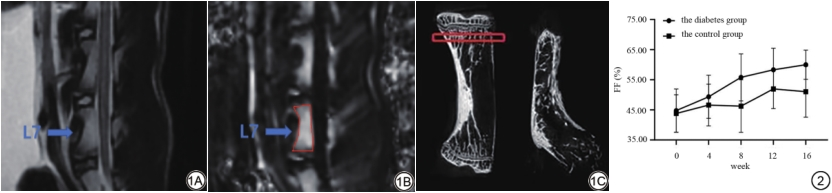

IDEAL-IQ图像分析由两位分别具有9年和5年骨肌影像诊断经验的副主任医师和主治医师在对兔子分组不知情的情况下独立完成。将Fat Fraction图像传入工作站(Advantage Workstation 4.6, GE Healthcare, Milwaukee, USA),为减少兔子的呼吸运动对图像的影响,选取呼吸运动伪影最小的map腰7椎体中心层面勾画感兴趣区。如图1所示,勾画兴趣区时,避开椎体边缘骨质、上下终板、椎基静脉丛,并记录所勾画区域内的脂肪分数(fat fraction, FF)。二人测量的结果取平均值记为椎体骨髓脂肪分数。

扫描后将原始图像导入三维重建软件NRecon(V1.7.4.2, Bruker, Germany)进行区域选择和图像重建,感兴趣区域设置为腰椎终板下1 mm区域(图1)。随后使用CT Analyser(1.18.8.0, Bruker, Germany)对重建区域进行骨小梁微结构测定。测量参数包括:骨矿物质密度(bone mineral density, BMD)、总体积(tissue volume, TV)、骨体积(bone volume, BV)、骨体积分数(percent bone volume, BV/TV)、总表面积(tissue surface, TS)、骨表面积(bone surface, BS)、骨表面积体积比(bone surface/volume ratio, BS/BV)、骨表面积总体积比(bone surface density, BS/TV)、骨小梁模式因子(trabecular pattern factor, Tb.Pf)、骨小梁结构模型指数(structure model index, SMI)、骨小梁厚度(trabecular thickness, Tb.Th)、骨小梁数量(trabecular number, Tb.N)、骨小梁分离度(trabecular separation, Tb.Sp)。

糖尿病组与对照组各时间节点兔椎体脂肪含量比服从正态分布,且组间数据方差齐。球形检验结果P>0.05,采用重复测量的方差分析,糖尿病组FF随时间变化呈上升趋势,且差异存在统计学意义(P<0.05),而对照组各时间点FF差异无统计学意义(P>0.05);糖尿病组与对照组腰椎骨髓FF在第16周差异有统计学意义(59.987±4.859 vs. 51.015±8.469,P<0.05)(图2)。